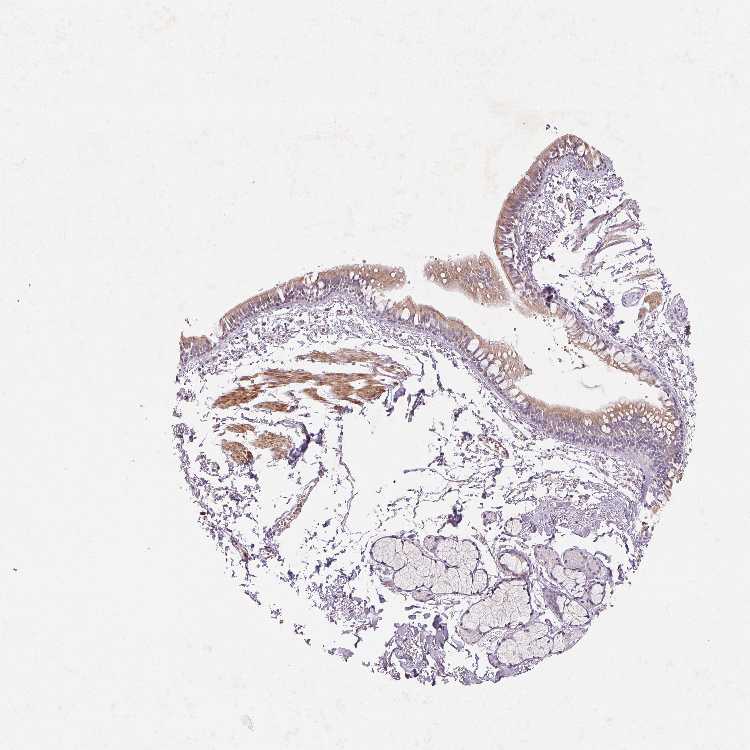

Antibody HPA064861

Respiratory epithelial cells Medium